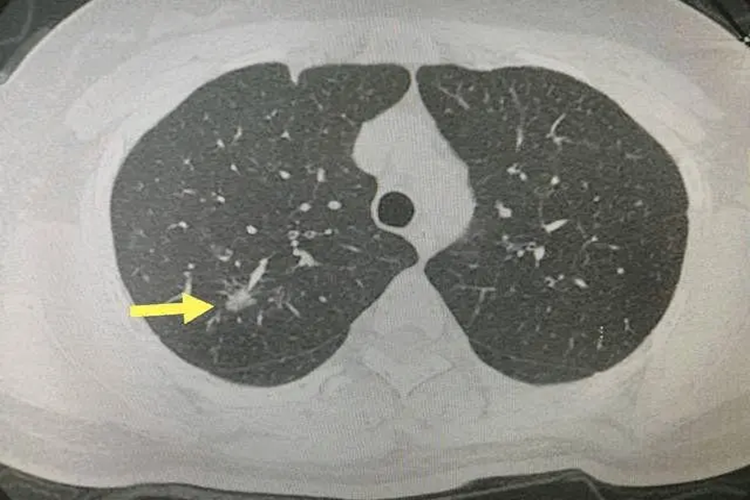

双肺结节LUNG-RADS2类是指在进行肺部CT扫描后,根据LUNG-RADS(肺癌筛查CT扫描的分级分类标准)系统评估,患者的双肺结节被归类为2类,通常被认为是良性结节或低风险结节。

- LUNG-RADS2类肺结节的恶性概率极低,一般小于1%。这类结节通常包括钙化灶、含脂质的结节、直径小于5mm的实性微小结节,以及球形肺不张等。其形态规则,边缘清晰,密度均匀,不会压迫到周围肺组织,也不会产生明显的临床症状。这类结节的增长速度非常缓慢,甚至可能在多年内无明显变化。